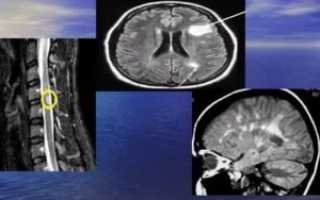

| Очаги демиелинизации на МРТ до и после лечения.Через 4 месяца от начала лечения видно уменьшение очагов – ремиелинизация(диагноз – рассеянный склероз, протекавший на фоне инфекции вирусомЭпштейн-Барр, микоплазмой и хламиией). Чем раньше начато лечение – темлучше прогноз на восстановление. |

| Очаг демиелинизации в веществе спинного мозга |

Ответ о происхождении и активности очагов демиелинизации в веществе головного мозга может дать МРТ с гадолиниевым контрастированием. Очаги, в которых демиелинизация идёт прямо сейчас, накапливают контрастное вещество, и это видно при МР-томографии.

Основной метод инструментальной диагностики – нейровизуализация. Очаги демиелинизации, расположенные в головном мозге, преимущественно выявляются при помощи исследования МРТ, на снимках отчетливо видны участки пораженной ткани диаметром не меньше 3 мм. Очаги демиелинизации в структурах ПНС обнаруживаются в ходе электромиографии. Ангиография показывает степень повреждения сосудов.